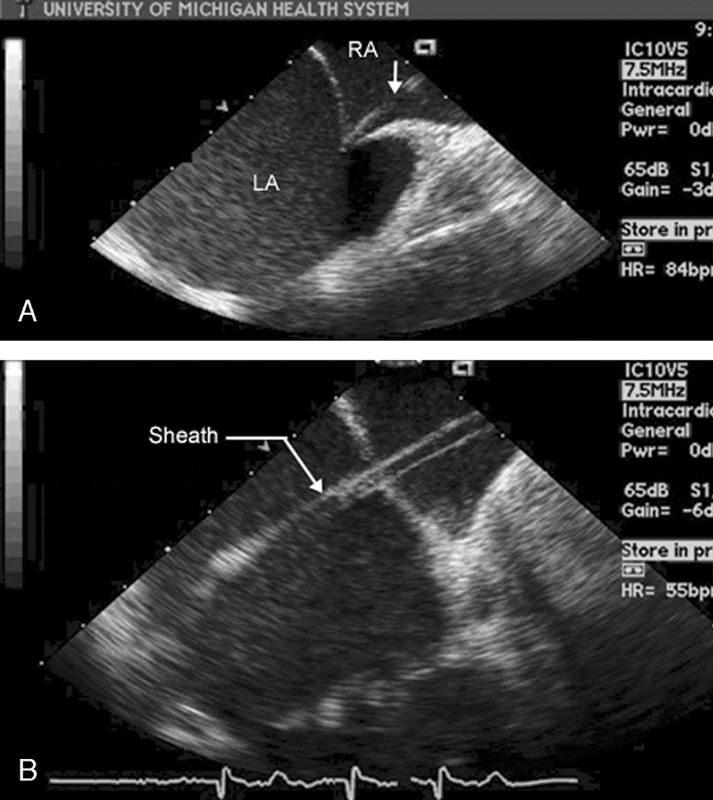

فحوصات تشخيصية لبعض امراض القلب والشرايين التاجية